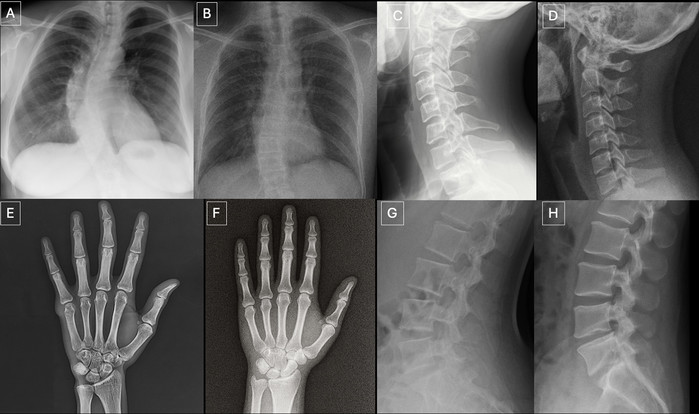

| ▲ 진짜일까요, 가짜일까요? 이 엑스레이 이미지 중 하나는 인공지능이 생성한 것이고, 다른 하나는 실제 이미지다. 어느 것이 진짜일까? (정답은 기사 끝부분에 있다) © Radiological Society of North America (RSNA)

| ▲ 해부학적 구조에 맞춰 촬영한 실제 방사선 사진과 GPT-4o로 생성한 방사선 사진 비교: (A) 실제 흉부 전후면 방사선 사진, (B) GPT-4o로 생성한 후전면 흉부 방사선 사진, (C) 실제 경추 측면 방사선 사진, (D) GPT-4o로 생성한 경추 측면 방사선 사진, (E) 실제 손 전후면 방사선 사진, (F) GPT-4o로 생성한 손 후전면 방사선 사진, (G) 실제 요추 측면 방사선 사진, (H) GPT-4o로 생성한 요추 측면 방사선 사진. 이 사진들은 GPT-4o가 다양한 해부학적 부위에서 방사선학적으로 타당한 이미지를 생성할 수 있음을 보여준다. (출처:Mar 24 2026 / The Rise of Deepfake Medical Imaging: Radiologists’ Diagnostic Accuracy in Detecting ChatGPT-generated Radiographs / Radiology) |